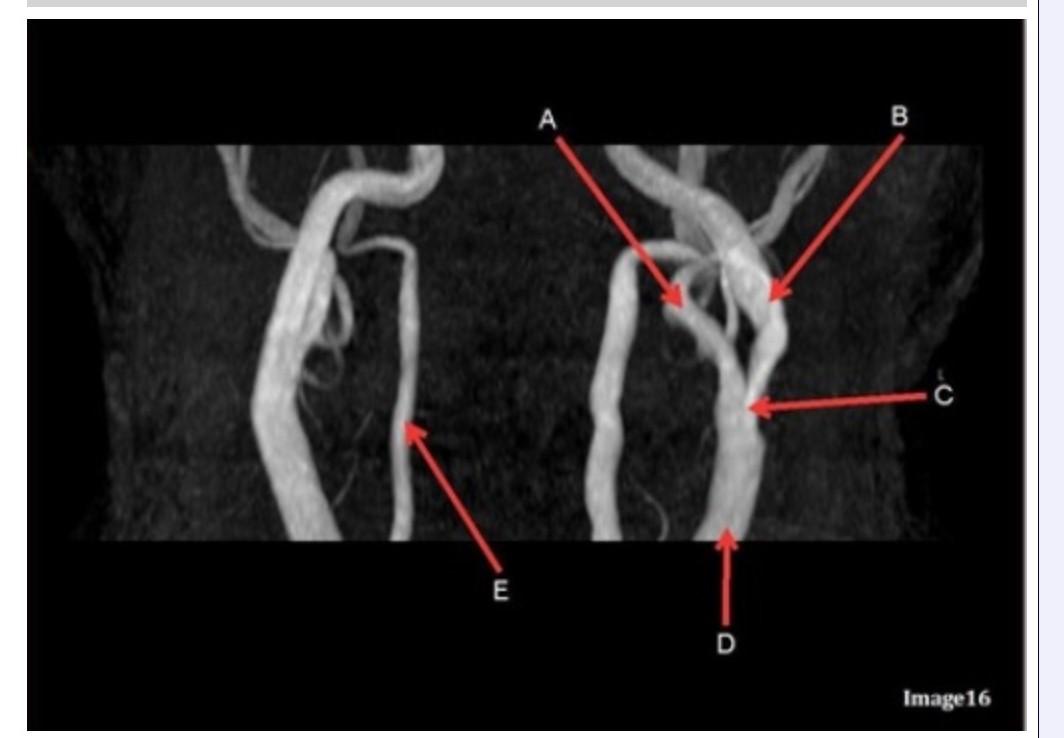

Letter B in Image 16 is pointing to:

A. Internal carotid artery

B. External carotid artery

C. Vertebral artery

D. Common carotid artery

E. Common carotid bifurcation

Letter E in Image 16 is responsible for blood supply to the:

A. Anterior brain

B. Posterior brain

C. Face

D. Upper extremities

Letter D in Image 16 is pointing to:

A. Internal carotid artery

B. External carotid artery

C. Vertebral artery

D. Common carotid artery

E. Common carotid bifurcation

Image 16 is an example of what type of MR image?

A. MR spectroscopy

B. MRA Circle of Willis

C. MRV intracranial circulation

D. MRA extracranial circulation

E. MRA intracranial circulation

Letter B in Image 16 is responsible for blood supply to the:

A. Anterior brain

B. Posterior brain

C. Face

D. Upper extremities

Letter E in Image 16 is pointing to:

A. Internal carotid artery

B. External carotid artery

C. Vertebral artery

D. Common carotid artery

Letter C in Image 16 is pointing to:

A. Internal carotid artery

B. External carotid artery

C. Vertebral artery

D. Common carotid artery

E. Common carotid bifurcation

Letter A in Image 16 is pointing to:

A. Internal carotid artery

B. External carotid artery

C. Vertebral artery

D. Common carotid artery

E. Common carotid bifurcation

Letter A in Image 16 is responsible for blood supply to the:

A. Anterior brain

B. Posterior brain

C. Face

D. Upper extremities